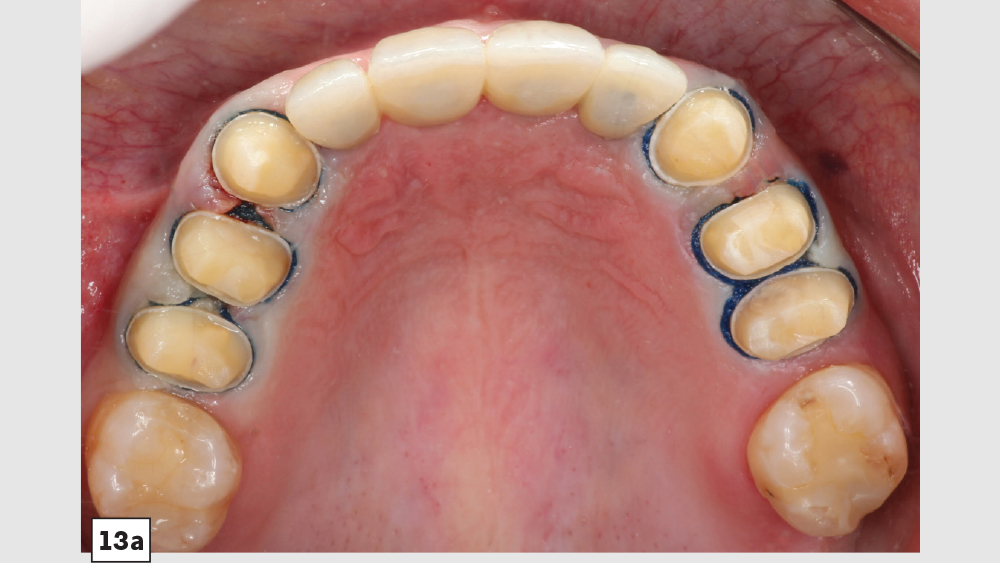

This patient came to me with four missing anterior teeth in positions #7–10. He had been missing these teeth for some time and was wearing a temporary denture to address the cosmetic issue this created. When he came to my practice, he was in a financial position to solve the problem permanently with implant restorations. Based upon the anterior space available and the fact that the patient’s surrounding tissue was in good health, I chose to move forward with Hahn™ Tapered Implants and BruxZir® Esthetic restorations.

There’s nothing more rewarding than when patients return to your office for additional dentistry because they were so thrilled with the results of the previous procedure you performed for them. This particular patient followed through with the additional treatment I had previously recommended.